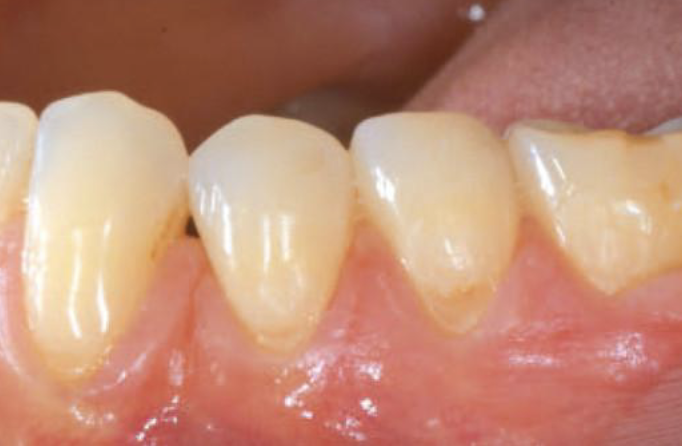

Kliniske kasus med hyaDENT BG Gingival recession (CAF)

Prof. Andrea Pilloni

1 year post-operative